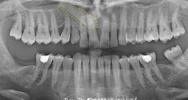

Diş Eksikliği

Diş ve Diş eti hastalıkları

Diş Çürükleri

Periimplantitis

Çene Kistleri

Periodontoloji

Ağız diş ve çene cerrahisi